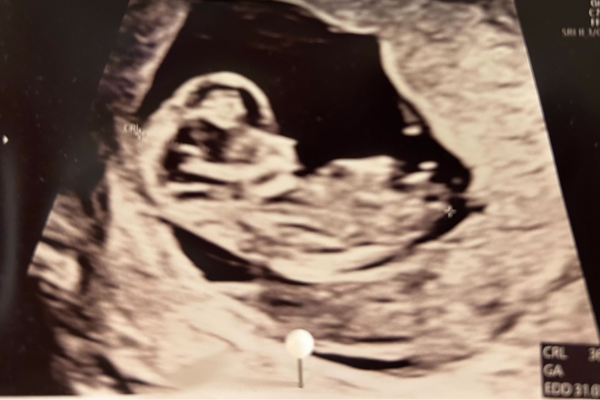

Barnets hoved udgør stadig halvdelen af dets totale størrelse. Den samlede længde er nu cirka 31-42 mm og vægten er mere end fordoblet siden sidste uge til cirka 5 gram. Allerede nu er alle organer på plads, men de er langt fra færdigudviklede. Den udvikling fortsætter de næste 30 uger, hvor organerne modnes i takt med, at barnet vokser. Hjertet, der har slået taktfast siden uge 6, er fuldt udviklet, men det er stadig meget lille. Mange af hjernens og nervesystemets funktioner er også allerede klar, og skjoldbruskkirtlen er begyndt at udskille hormonet thyroxin, der styrer cellernes energiomsætning. På fingre og tæer kan man se antydningen til led og bittesmå negle. Smagsløgene udvikles, og øjnene bevæger sig fremad for at finde deres plads. Barnet kan opfatte lys, men ikke blinke endnu. Nu dannes det indre øre, men det varer lidt, inden barnet kan høre.

På ultralyd er det nu meget let at se, at det er et lille menneske, du har i maven. Arme, ben, hænder og fødder ses tydeligt. Det er sjovt at se, hvor meget barnet kan bevæge sig. Selvom aktiviteten i din livmoder er stor, kan du sandsynligvis ikke mærke bevægelserne endnu. De fleste mærker liv for første gang mellem uge 18 og 22. Bevægelserne kan føles som små bobler eller små svage puf. Hvis du er gravid for første gang, kan det være du mærker liv lidt senere, mens mødre der har født før, kan mærke liv før uge 18.